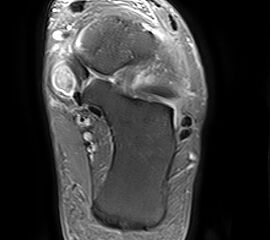

Magnet-Resonanz-Tomographie

Rupturierte Tibialis posterior Sehne in den coronaren, protonensensitiven Schichten. Bei diskreten Läsionen erhöht die Gabe von Kontrastmittel die Beurteilbarkeit.

Abbildung 6g

Die Magnet-Resonanz-Tomographie (MRT) eignet sich besonders zur Darstellung der Tenosynovitis und Degeneration der Tibialis posterior Sehne. Hinsichtlich Sensitivität und Spezifität ist das MRT dem CT insbesondere bei Sehnenlängsrupturen überlegen 23. Die normale Sehne erscheint auf dem MRT mit schwarzem, homogenem Signal und ovaler Form, zwei bis dreimal dicker als die Sehne des M. flexor digitorum longus. Ein schmaler Flüssigkeitsaum < 1-2 mm ist physiologisch. Bei der Tenosynovitis ist der Saum deutlich breiter und neben dem Ödem in der Sehnenmatrix am besten auf den T2-Wichtungen zu erkennen. Strukturelle Veränderungen der Sehnenmatrix, wie z.B. Partial- oder Längsrupturen sind besser auf den T1-Wichtungen zu sehen. Nach der Sehnenhypertrophie im Stadium I der Erkrankung kommt es jeweils mit wenig oder keiner Begleitentzündung im Stadium II zur Elongation und Abnahme des Sehnendurchmessers und im Stadium III zur Ruptur, welche im MRT gut ersichtlich sind. Hingegen finden sich mit zunehmender Dauer der Erkrankung Entzündungszeichen infolge fibulocalcanearen Impingements und lateral betonter OSG-Degeneration und Arthrose v.a. auf den T2-Wichtungen.

Weitere begleitende Befunde, die mit der Planovalgus Deformität einhergehen, sind Fibrose im Sinus tarsi, fehlende Ligamenti interosseus und cervicalis und eine fettige Degeneration des Tibialis posterior Muskels. Für die Operationsplanung ebenfalls wichtig ist die MRT Beurteilung des Ligamentum calcaneonaviculare mediale und inferiore (Spring ligament).